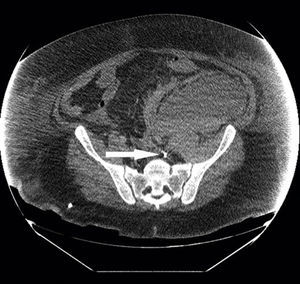

A patient underwent CRRT throw a left femoral vein catheter (34cm–13.5F). Immediately after the insertion we detected problems in the circuit blood flow and the patient deteriorated. A CT scan showed the tip of the catheter in the left lumbar vein beside a retroperitoneal haematoma (Fig. 1). Another patient (same catheter and insertion technique) showed persistent blood flow problems and in a CT scan the catheter was detected in an accessory left hemiacygos vein and already visible in the plain abdominal X-ray (Fig. 2). Because presumably an eco-directed insertion would not have prevented these anomalous locations, in the event of serious flow problems, a radiologic exploration can help ruling out this unusual and scarcely reported malposition that demands immediate withdrawal of the catheter.